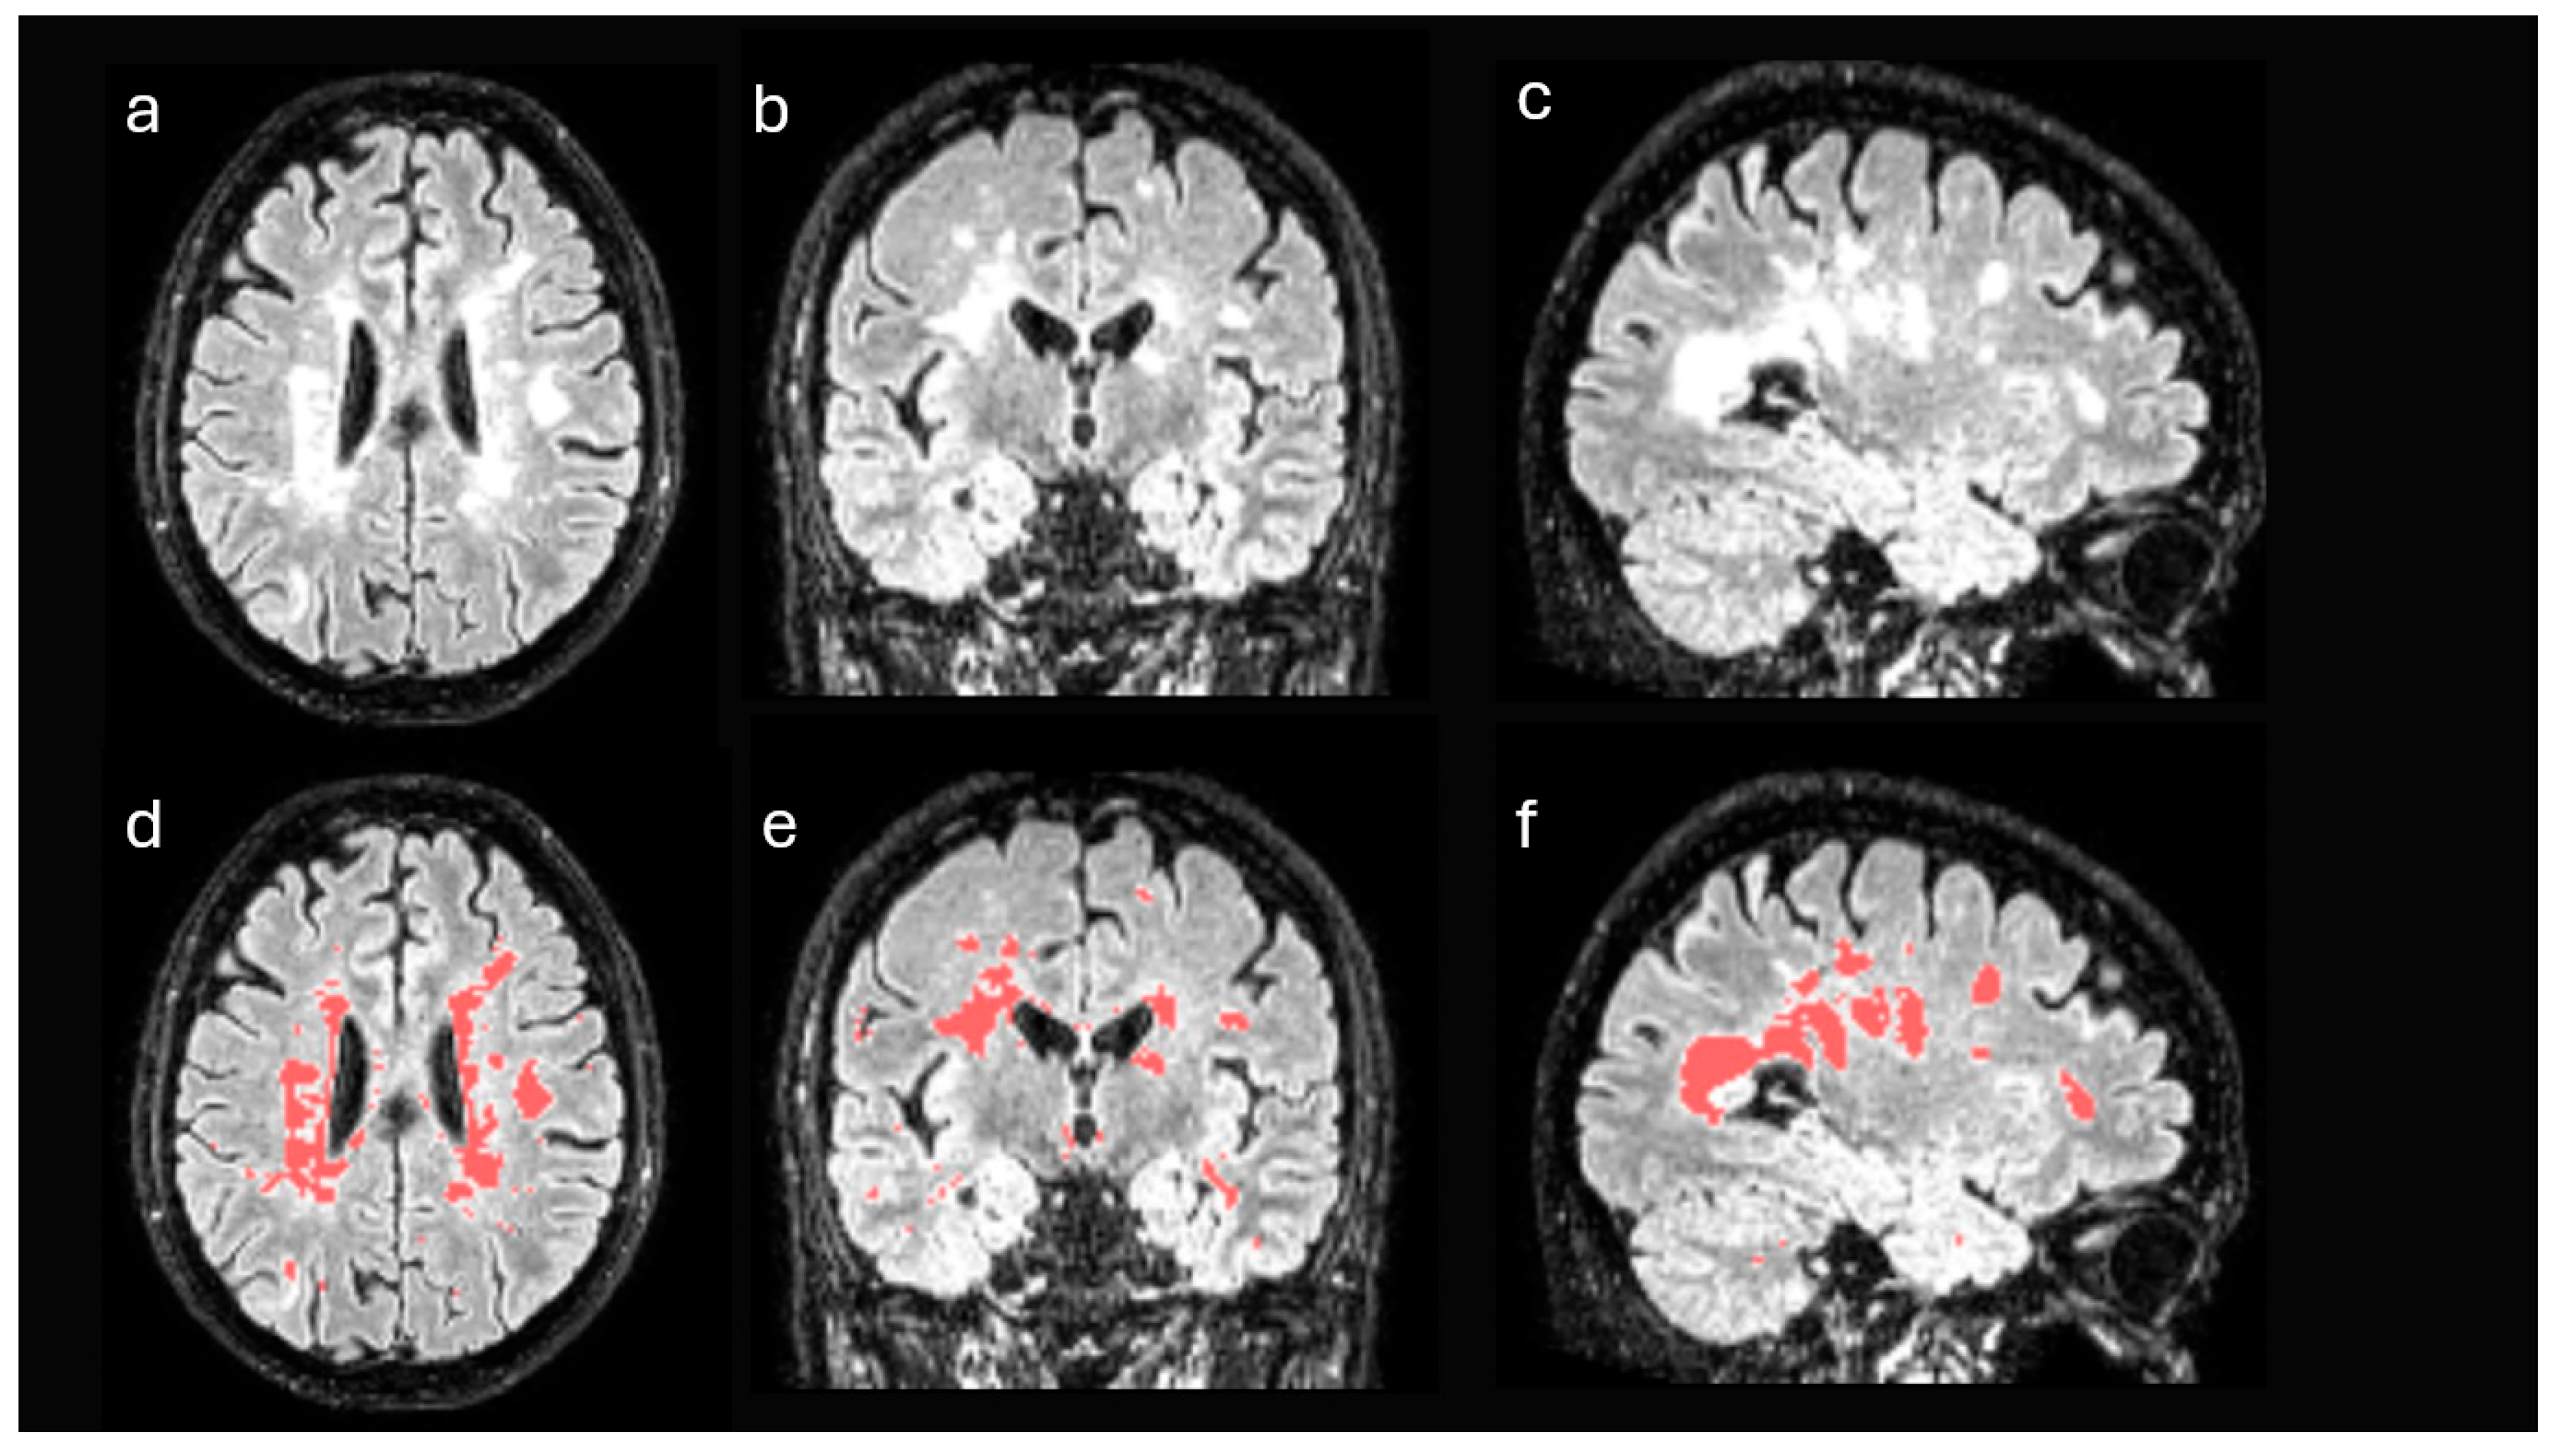

2.3. Brain Magnetic Resonance Imaging

2.5. Neuroimaging Pre-Processing and Analysis